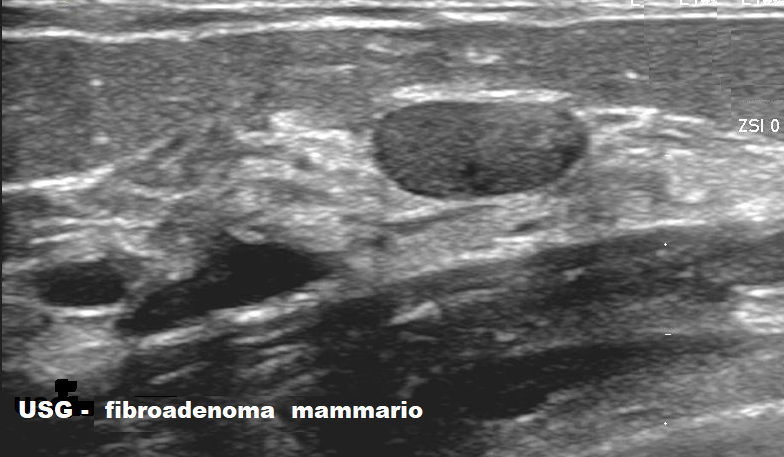

Fibroadenoma al Seno: sintomi, diagnosi e trattamento

Fibroadenoma al seno: sintomi, diagnosi, quando preoccuparsi e cosa fare Il fibroadenoma al seno è uno dei noduli benigni mammari più comuni. Si presenta spesso come una formazione solida, liscia, ben delimitata e mobile alla palpazione, ed è più frequente … Continua a leggere